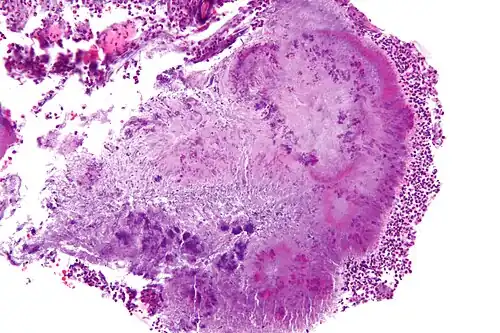

Gallery

Micrograph of actinomycosis, H&E stain- Micrograph of actinomycosis, GMS stain